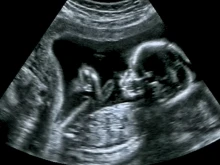

Companies admit illegal fetal tissue sales, end California operations. Is Planned Parenthood next?

The trade in fetal tissue from aborted babies proved costly for two bioscience companies who will admit fault, cease California... Read more